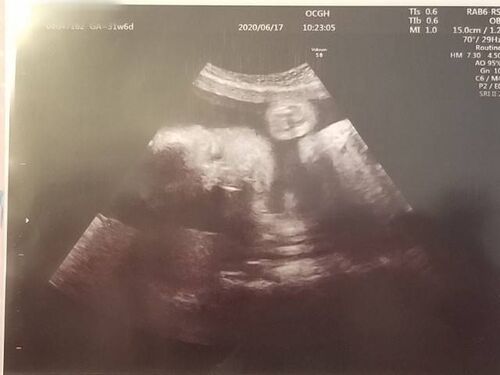

【31w6d】心臓エコーラスト!8ヶ月最終週でまさかの逆子に…!!

妊娠8ヵ月最終週。最後の『心エコー』の記録です。お腹の赤ちゃんの心疾患について。